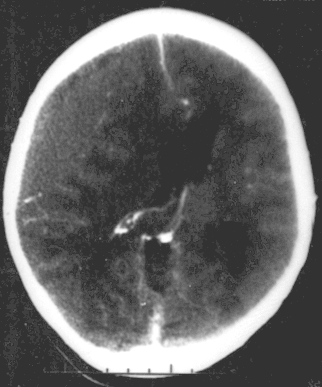

Hematoma epidural

Es un sangrado entre la parte interior del cráneo y la cubierta externa del cerebro (denominada "duramadre").

Un sangrado rápido causa una acumulación de sangre (hematoma) que presiona el cerebro. La presión dentro de la cabeza (presión intracraneal, PI) aumenta rápidamente. Esta presión puede ocasionar una lesión cerebral adicional.